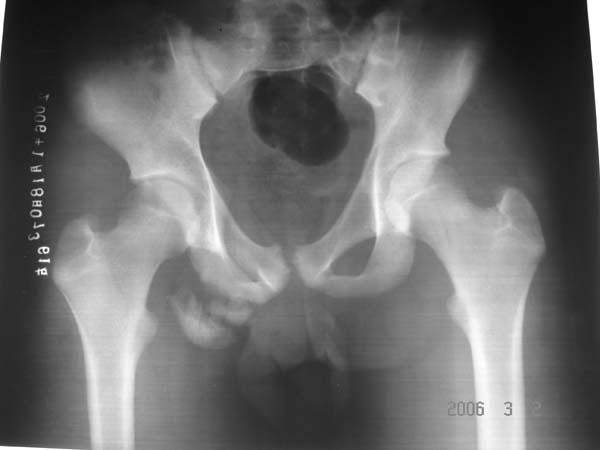

男性,15岁,半年前曾有做运动摔伤史,伤后左肢麻木,一天后恢复,两个月后因右臀部隐痛照片示右坐骨下骨性密度影,现复查见骨性影无明显改变。求助诊断!

坐骨撕脱骨折.

坐骨撕脱性骨折

明显坐骨骨折。

坐骨结节骨折

坐骨粗大,有瘤骨,基地部有囊状骨缺损。不应为外伤史迷惑,应考虑外生软骨瘤病或骨膜硬纤维瘤。请勿见笑。

坐骨骨折!骨盆有畸形!